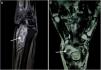

(A) T2W FAT SAT sagittal image show a well defined fluid intensity collection seen along the flexor tendon sheath with presence of hypointense layered rice grain (white arrow) shaped within it suggestive of tenosynovitis with multiple loose bodies. (B) T2W Coronal images show well defined fluid intensity collection anterior to the wrist joint along the flexor tendon sheath suggestive of tenosynovitis. Multiple layered hypointense loose bodies like rice grain are seen within it (arrow).

A 50-year-old lady came with progressive pain and isolated swelling of the right wrist of 9 months duration. Physical examination revealed an oblong swelling on the volar aspect of wrist extending into the forearm. Attempted active flexion at the wrist was painful though passive range of movement was normal. Laboratory investigations showed raised erythrocyte sedimentation rate of 50mm/h. Radiograph of the wrist was normal. MRI revealed well-defined fluid intensity collection along the flexor tendon sheath with presence of hypointense-layered lucencies within suggestive of tenosynovitis with rice bodies (Fig. 1A and B). The adjacent bone and soft tissues were normal. Fluid obtained by ultrasound-guided aspiration from the tenosynovial swelling was positive for Acid Fast Bacilli. Culture grew Mycobacterium Tuberculosis and hence, diagnosis of tuberculosis was reached. The patient did not have diabetes and was not on any immunosuppressive drugs. Serology for Human Immunodeficiency Virus (HIV) was non-reactive. The patient responded to six months of anti-tuberculous therapy with complete resolution of pain and swelling.